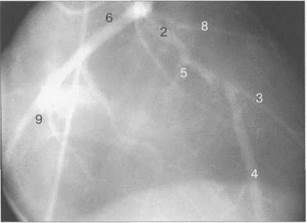

Анатомия коронарных артерий: КТ-изображения

Раздел: Снимки успеха